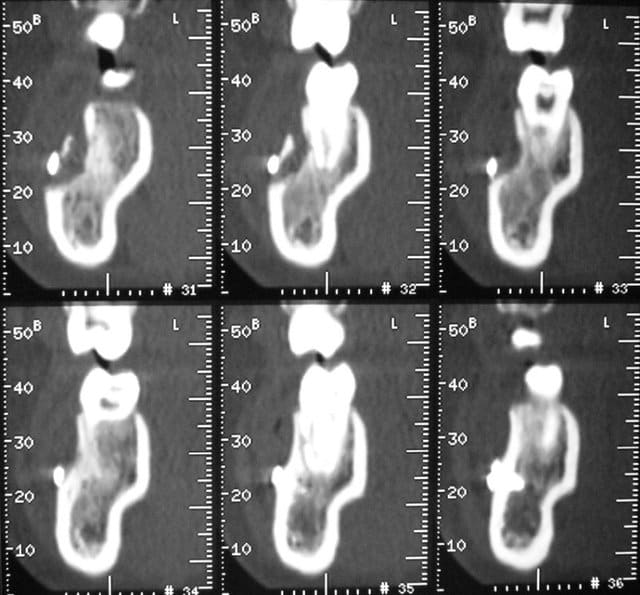

Il semble bien que la radio (et les coupes scan) que tu présentes appartiennent à un cas de traumatologie ou de chirurgie orthognathique. Ce ne sont certes pas des ancrages orthodontiques. Ne mélangeons pas tout, svp ! (à moins que ce ne soit de la provocation ou de la mauvaise foi, cher Bjc, mais je n'ose quand même pas penser cela de ta part).

Puisque j'ai eu la chance ( moi et non pas le patient) d'etre confronté à cette situation, je l'ai pris pour éxemple, pour montrer que ces techniques ne sont pas éxemptes de risques. Tout comme l'anesthésie intra-osseuse.

C'est un cas extrème, certes, mais ce sont les plus parlants.

Cas extrême ? J’ai mieux que cela (fig. jointes).

Ami d’Eugénol qui lis ces lignes, rassure-toi ! Ce sont des cas de chirurgie maxillo-faciale qui n’ont rien à voir avec les cas d’ancrages osseux orthodontiques, ni avec la discussion en cours. Notre bon Bjc a introduit cet aparté car il aime bien les facéties.